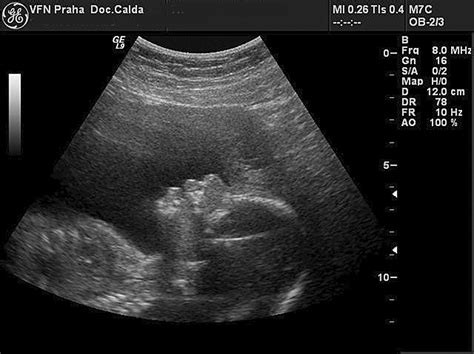

Ultrazvukové merania: Orientácia, nie presnosť

Informácie o veľkosti bábätka sa mamičky dozvedajú po ultrazvukovom vyšetrení. Ak sa namerané hodnoty nezhodujú s ideálnym vývojom, môže to u budúcich mamičiek vyvolať obavy, najmä ak dieťa zaostáva vo vývoji aj viac ako týždeň. V takýchto prípadoch nie je dôvod na paniku.

Jednou z príčin nepresných meraní môže byť nesprávne určenie dátumu pôrodu. Napriek pokročilej technológii sa lekárom môže stať, že neodhadnú presný dátum počatia. Vtedy dochádza k skresleniu vývoja, ktoré v skutočnosti nie je reálne, pretože dieťa sa vyvíja podľa skutočného dátumu počatia.

Ďalšou príčinou nepresných údajov môže byť nesprávne meranie. Bábätko v brušku je často v nepohodlných polohách, čo môže znemožniť presné zmeranie. Preto je dôležité brať tieto hodnoty len orientačne a sústrediť sa na to, že dieťatko krásne rastie a napreduje.